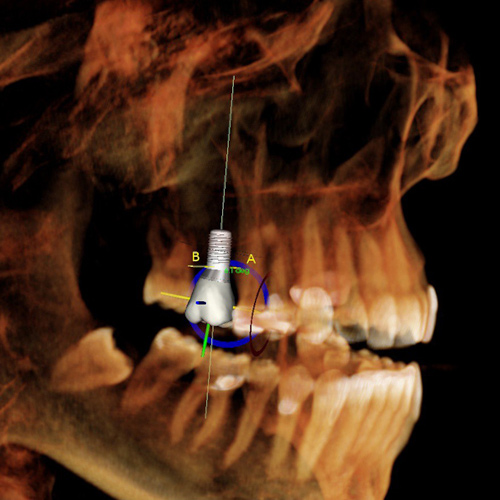

La perforation du sinus lors de la pose de l'implant dentaire

La perforation du sinus est rare et n'est pas forcément due à un mauvais geste du chirurgien-dentiste. Le tissu osseux n'est pas une surface plane mais irrégulière et le nerf peut parfois avoir des bifurcations. Le forage en implantologie traditionnelle est large et la marge d'erreur moins importante. La perforation du sinus peut être gérée assez facilement mais nécessite plusieurs visites.